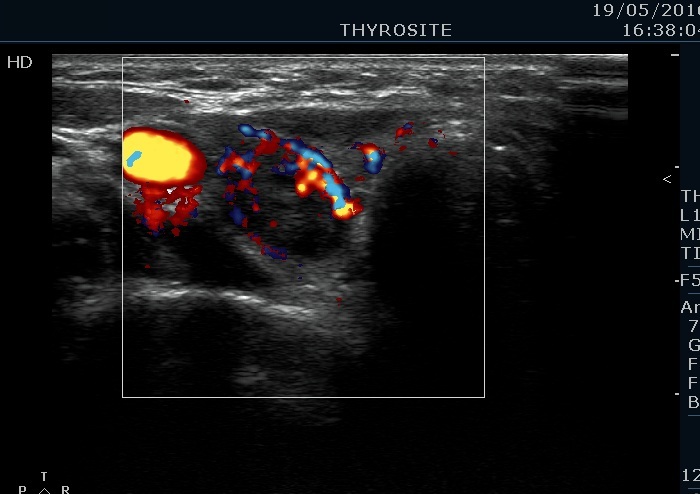

100 consecutive cases of papillary cancer - case 027 (ultrasonographic picture 5)

Lower part of the right lobe, transverse view, color Doppler mode. This is an irregularly increased, suspicious vascular pattern.